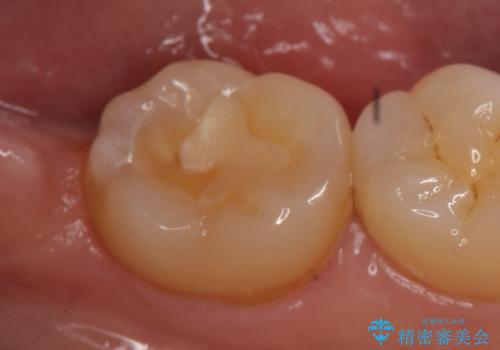

- 右下の奥歯が冷たいものを飲むとしみるので診て欲しいといらっしゃった方の症例です。

古い樹脂を除去し、PGA(ゴールド)インレーによる修復を行いました。